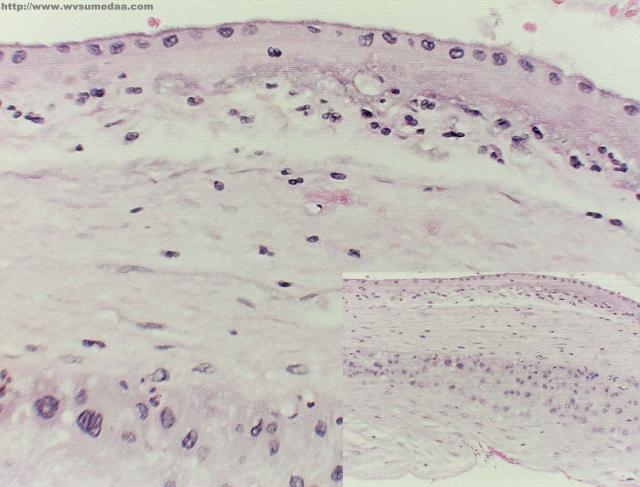

Sezione membrana amniotica

(ANSA) – MILANO, 11 GIU – Dallo strato piu’ interno della placenta umana, chiamato membrana amniotica, si puo’ ricavare materiale utile per riparare le cornee dei bambini danneggiate da traumi o infiammazioni. E’ una delle novita’ che gli esperti stanno discutendo al convegno nazionale della Societa’ di oftalmologia pediatrica (Siop), che si e’ aperto oggi a Milano. La membrana amniotica, spiegano infatti i ricercatori, fornisce elementi nutritivi che migliorano il decorso dei processi infiammatori che possono colpire la cornea. Tra gli altri temi su cui si concentrera’ il convegno ci sono le malattie oculari legate a disfunzioni del metabolismo, cosi’ come le nuove tecniche di diagnosi precoce e di riabilitazione visiva. ”Queste patologie – spiega Elena Piozzi, direttore dell’oculistica pediatrica all’ospedale Niguarda di Milano – sono piu’ frequenti nell’adulto, ma nel bambino sono molto piu’ gravi, perche’ qualsiasi tipo di intervento in eta’ infantile va supportato da un’adeguata attivita’ di rieducazione visiva, con tempi di recupero piu’ lunghi e maggiori costi sociali. Inoltre la vista e’ il primo canale di apprendimento, quindi piu’ sono gravi e precoci questi disturbi tanto maggiore e’ la probabilita’ di avere un ritardo psicomotorio”.